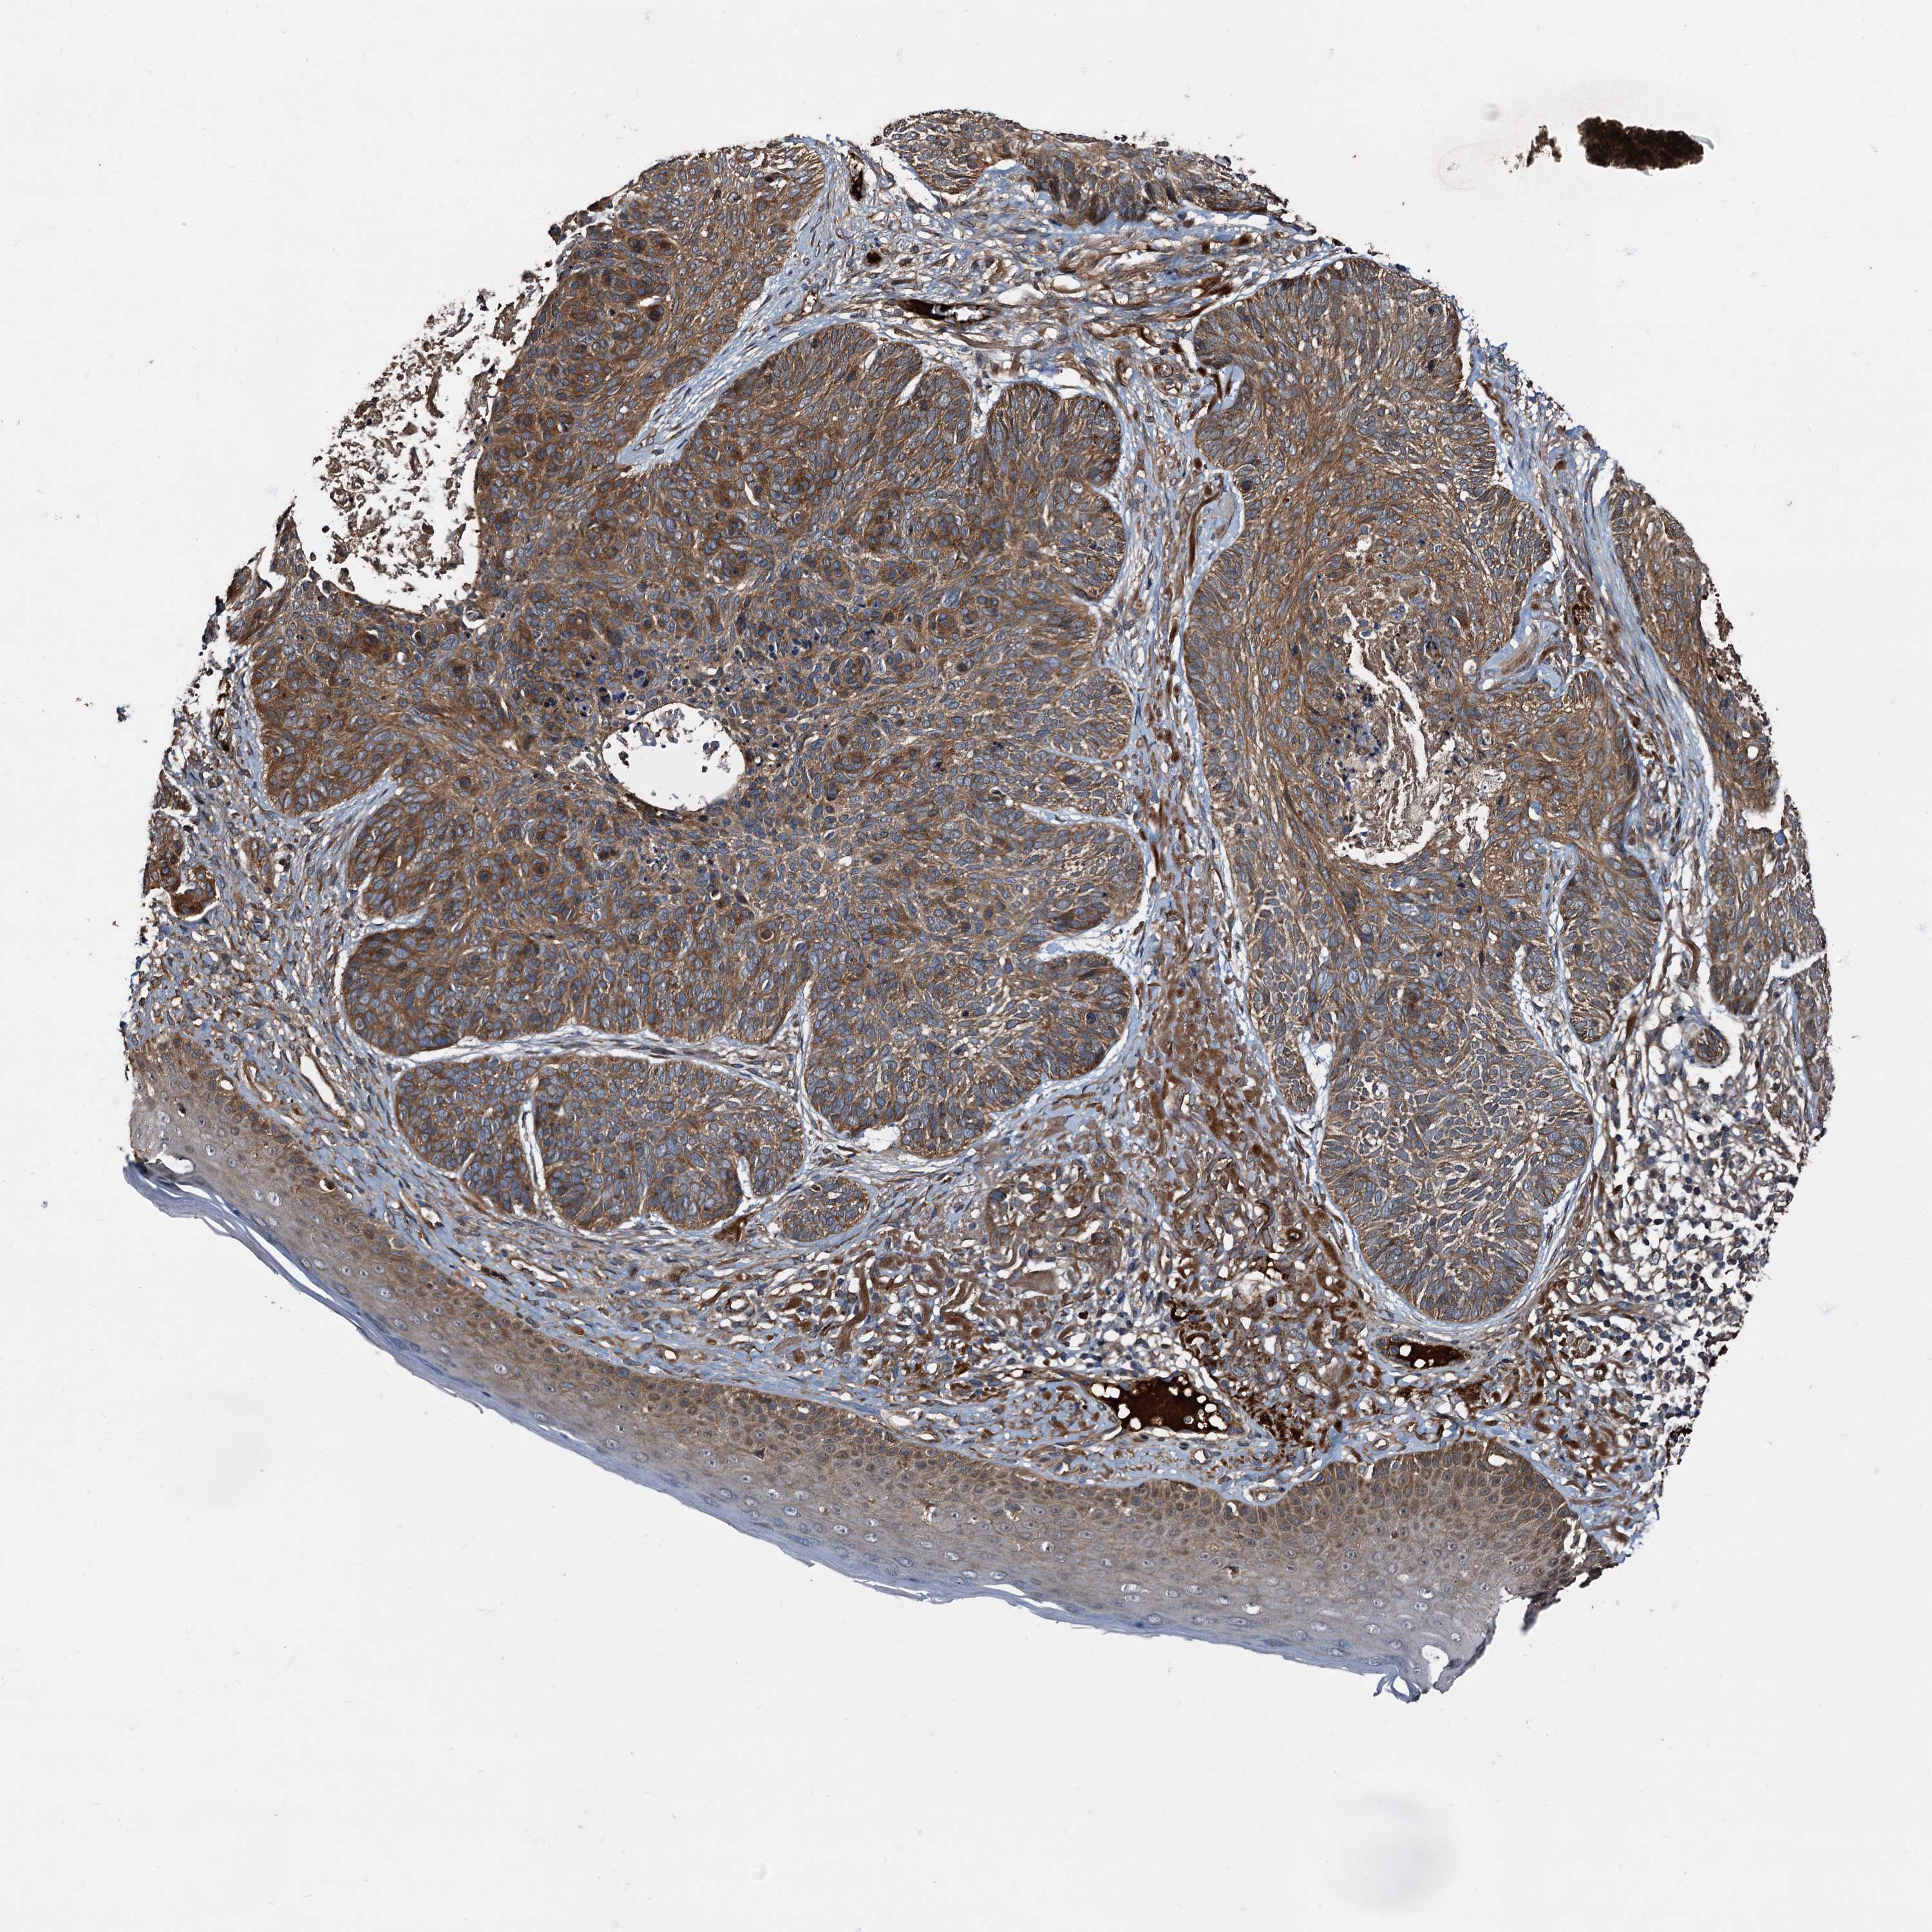

Basal cell and squamous cell cancer

SKIN CANCER - Protein expressioni

A mouse-over function shows sample information and annotation data. Click on an image to view it in a full screen mode. Samples can be filtered based on level of antibody staining by selecting one or several of the following categories: high, medium, low and not detected. The assay and annotation is described here.

Each image is clickable and will lead to virtual microscopy that enables deeper exploration of all samples and also displays staining intensity scores, fraction scores and subcellular localization as well as patient and tissue information for each sample.

Antibody HPA039259

Antibody HPA039260

Basal cell carcinoma

Squamous cell carcinoma, NOS

Squamous cell carcinoma, metastatic, NOS